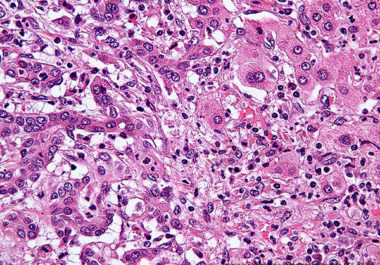

Post-surgery Option for Liver Cancer

New study finds drug combination after surgery helps prevent recurrence in liver cancer patients.

New study finds drug combination after surgery helps prevent recurrence in liver cancer patients.

The FDA approved a combination of an immunotherapy and a therapeutic that can stop tumors from growing blood vessels for certain patients with liver cancer.

The FDA approved using a combination of nivolumab and ipilimumab, two immune checkpoint inhibitors, to treat certain patients with hepatocellular carcinoma.

The FDA expanded the use of the immunotherapy pembrolizumab to include the treatment of certain patients with liver cancer.